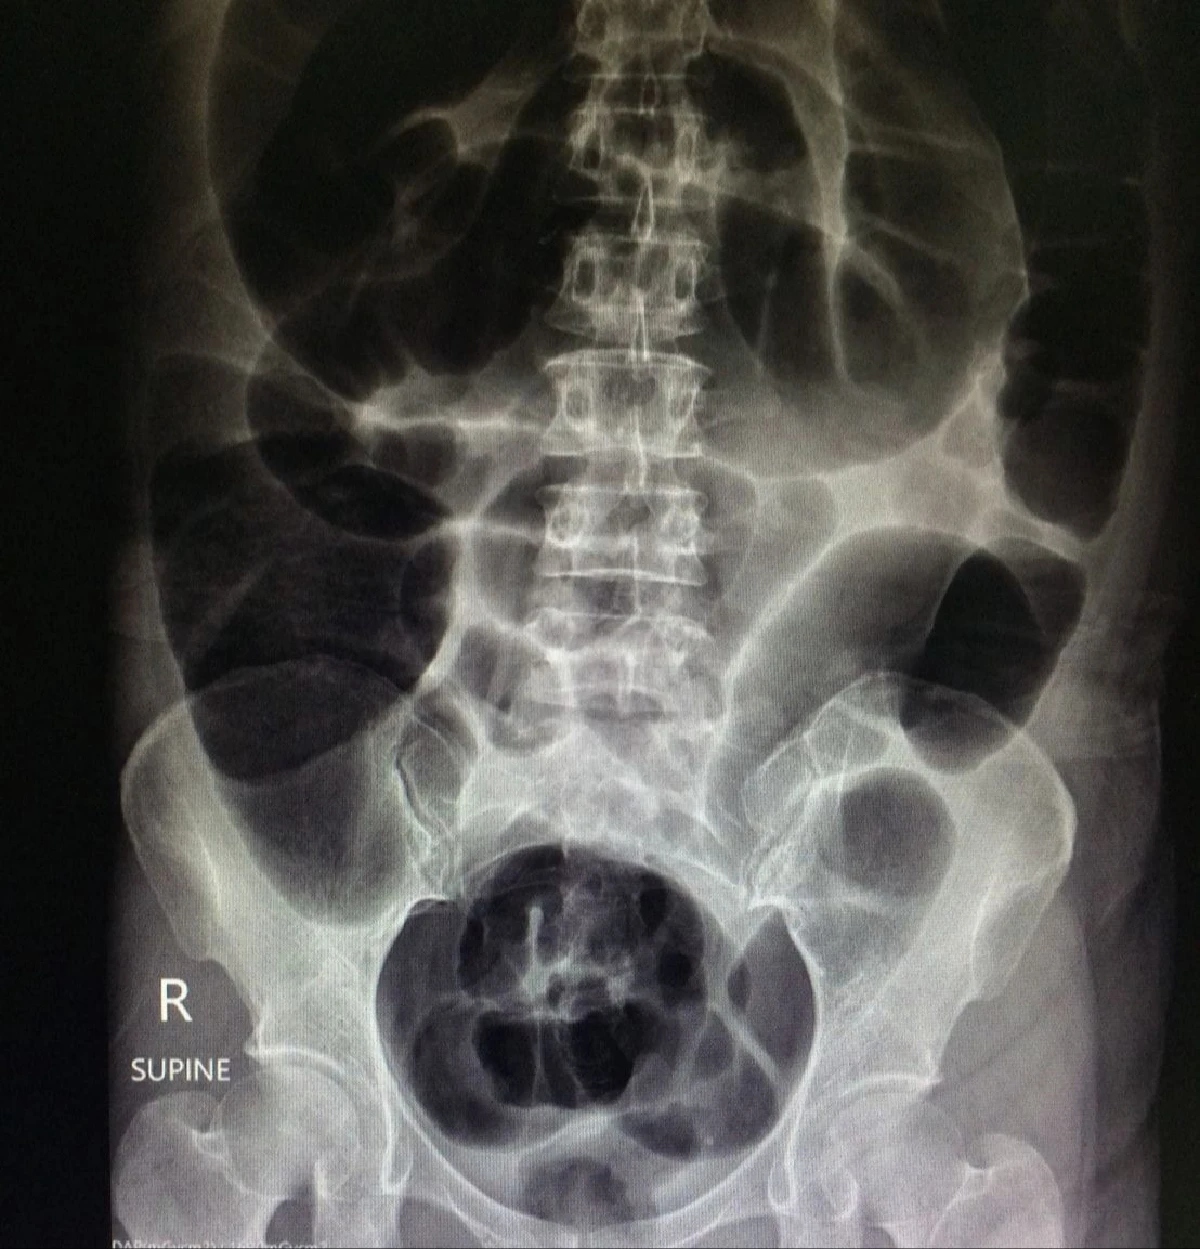

เมื่อวันที่ 18 ส.ค. นพ.อารักษ์ วงศ์วรชาติ ผู้อำนวยการโรงพยาบาลสิชล จังหวัดนครศรีธรรมราช โพสต์ภาพและข้อความเตือนภัย กรณีการเกิดอาการท้องผูกเรื้อรังจนลำไส้อุดตัน ว่า ท้องผูกเรื้อรังจนลำไส้อุดตัน ตัวอย่างเคสมีอาการท้องผูก 3-4 วัน จึงถ่ายสักครั้ง อุจจาระแข็ง ต้องออกแรงเบ่ง จึงกินยาระบาย สวนสบู่เป็นประจำ จนในที่สุดเกิดลำไส้อุดตัน ปวดท้อง ท้องอืดมาก ต้องผ่าตัดฉุกเฉิน ตัดลำไส้บางส่วนที่โป่งพองอย่างมากทิ้งไปแล้วต่อลำไส้ใหม่